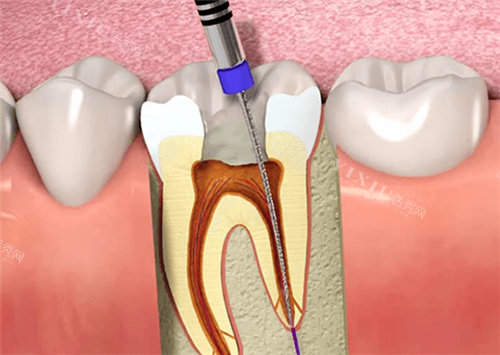

根管治疗:870 元起